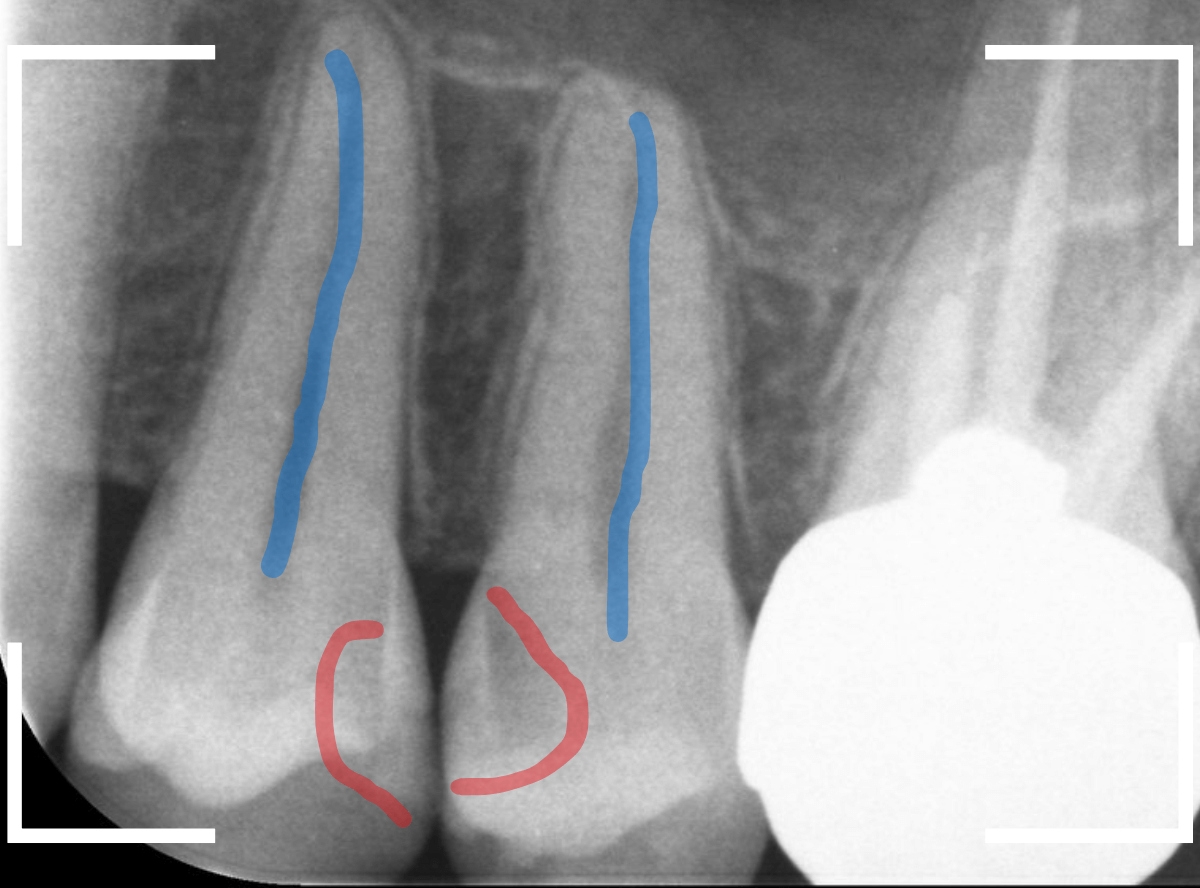

レントゲン写真で確認します。

青い線が歯の神経、赤い線が虫歯と思われる部分です。

2本とも、神経に達してしまいそうな大きな虫歯であると思われます。